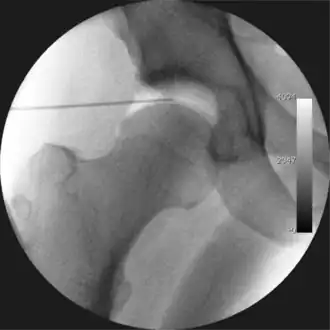

Figure 4. A needle is passed into the joint, breaking the 'suction seal', and allowing further distraction of the hip joint with minimal extra traction -

The next step is to insert a fine needle under x-ray guidance into the hip joint. This breaks the 'suction seal' of the joint and allows further distraction if necessary (see fig 4). The surgeon wishes to see the ball move out the socket by approximately 1 cm, so that access to the hip joint can be achieved with minimal risk of damage to the joint surfaces. Most surgeons will inject fluid into the joint at this stage, again to ensure that there is enough space between the ball and socket for safe instrument access. This needle is then removed. The next step is placement of the 'portals', or the small holes made to pass instruments into the joint. This is achieved by again passing a fresh hollow needle into the joint under x-ray control, usually in a slightly different position. The reason for this is so the surgeon can ensure that the needle, and subsequent cannulae do not penetrate and damage the acetabular labrum or cartilage joint surfaces (see fig. 5). Again, surgeons will have their own preferences as to their preferred placement. Through this hollow needle, a long thin flexible guide wire is passed into the joint, and the needle is removed over it, leaving the guide wire in situ. A small cut in the skin is made around the wire, to allow for larger cannulae to be placed over the wire through the portal. The wire therefore guides the larger cannulae into the joint. The most common external diameters of cannulae used are between 4.5 and 5.5 mm. Once the surgeon is satisfied that the cannula is in the correct position, by a combination of feel and x-ray guidance, the guide wire can be withdrawn. Once the first portal is correctly placed, any further portals may be created once the camera is in position, to ensure that they are placed with minimal risk to the joint surfaces. This process can be repeated to gain as many points of entry to the hip joint as the surgeon requires, normally between two and four. Certain of these entry points will be used for the viewing arthroscope and others for operating instruments.